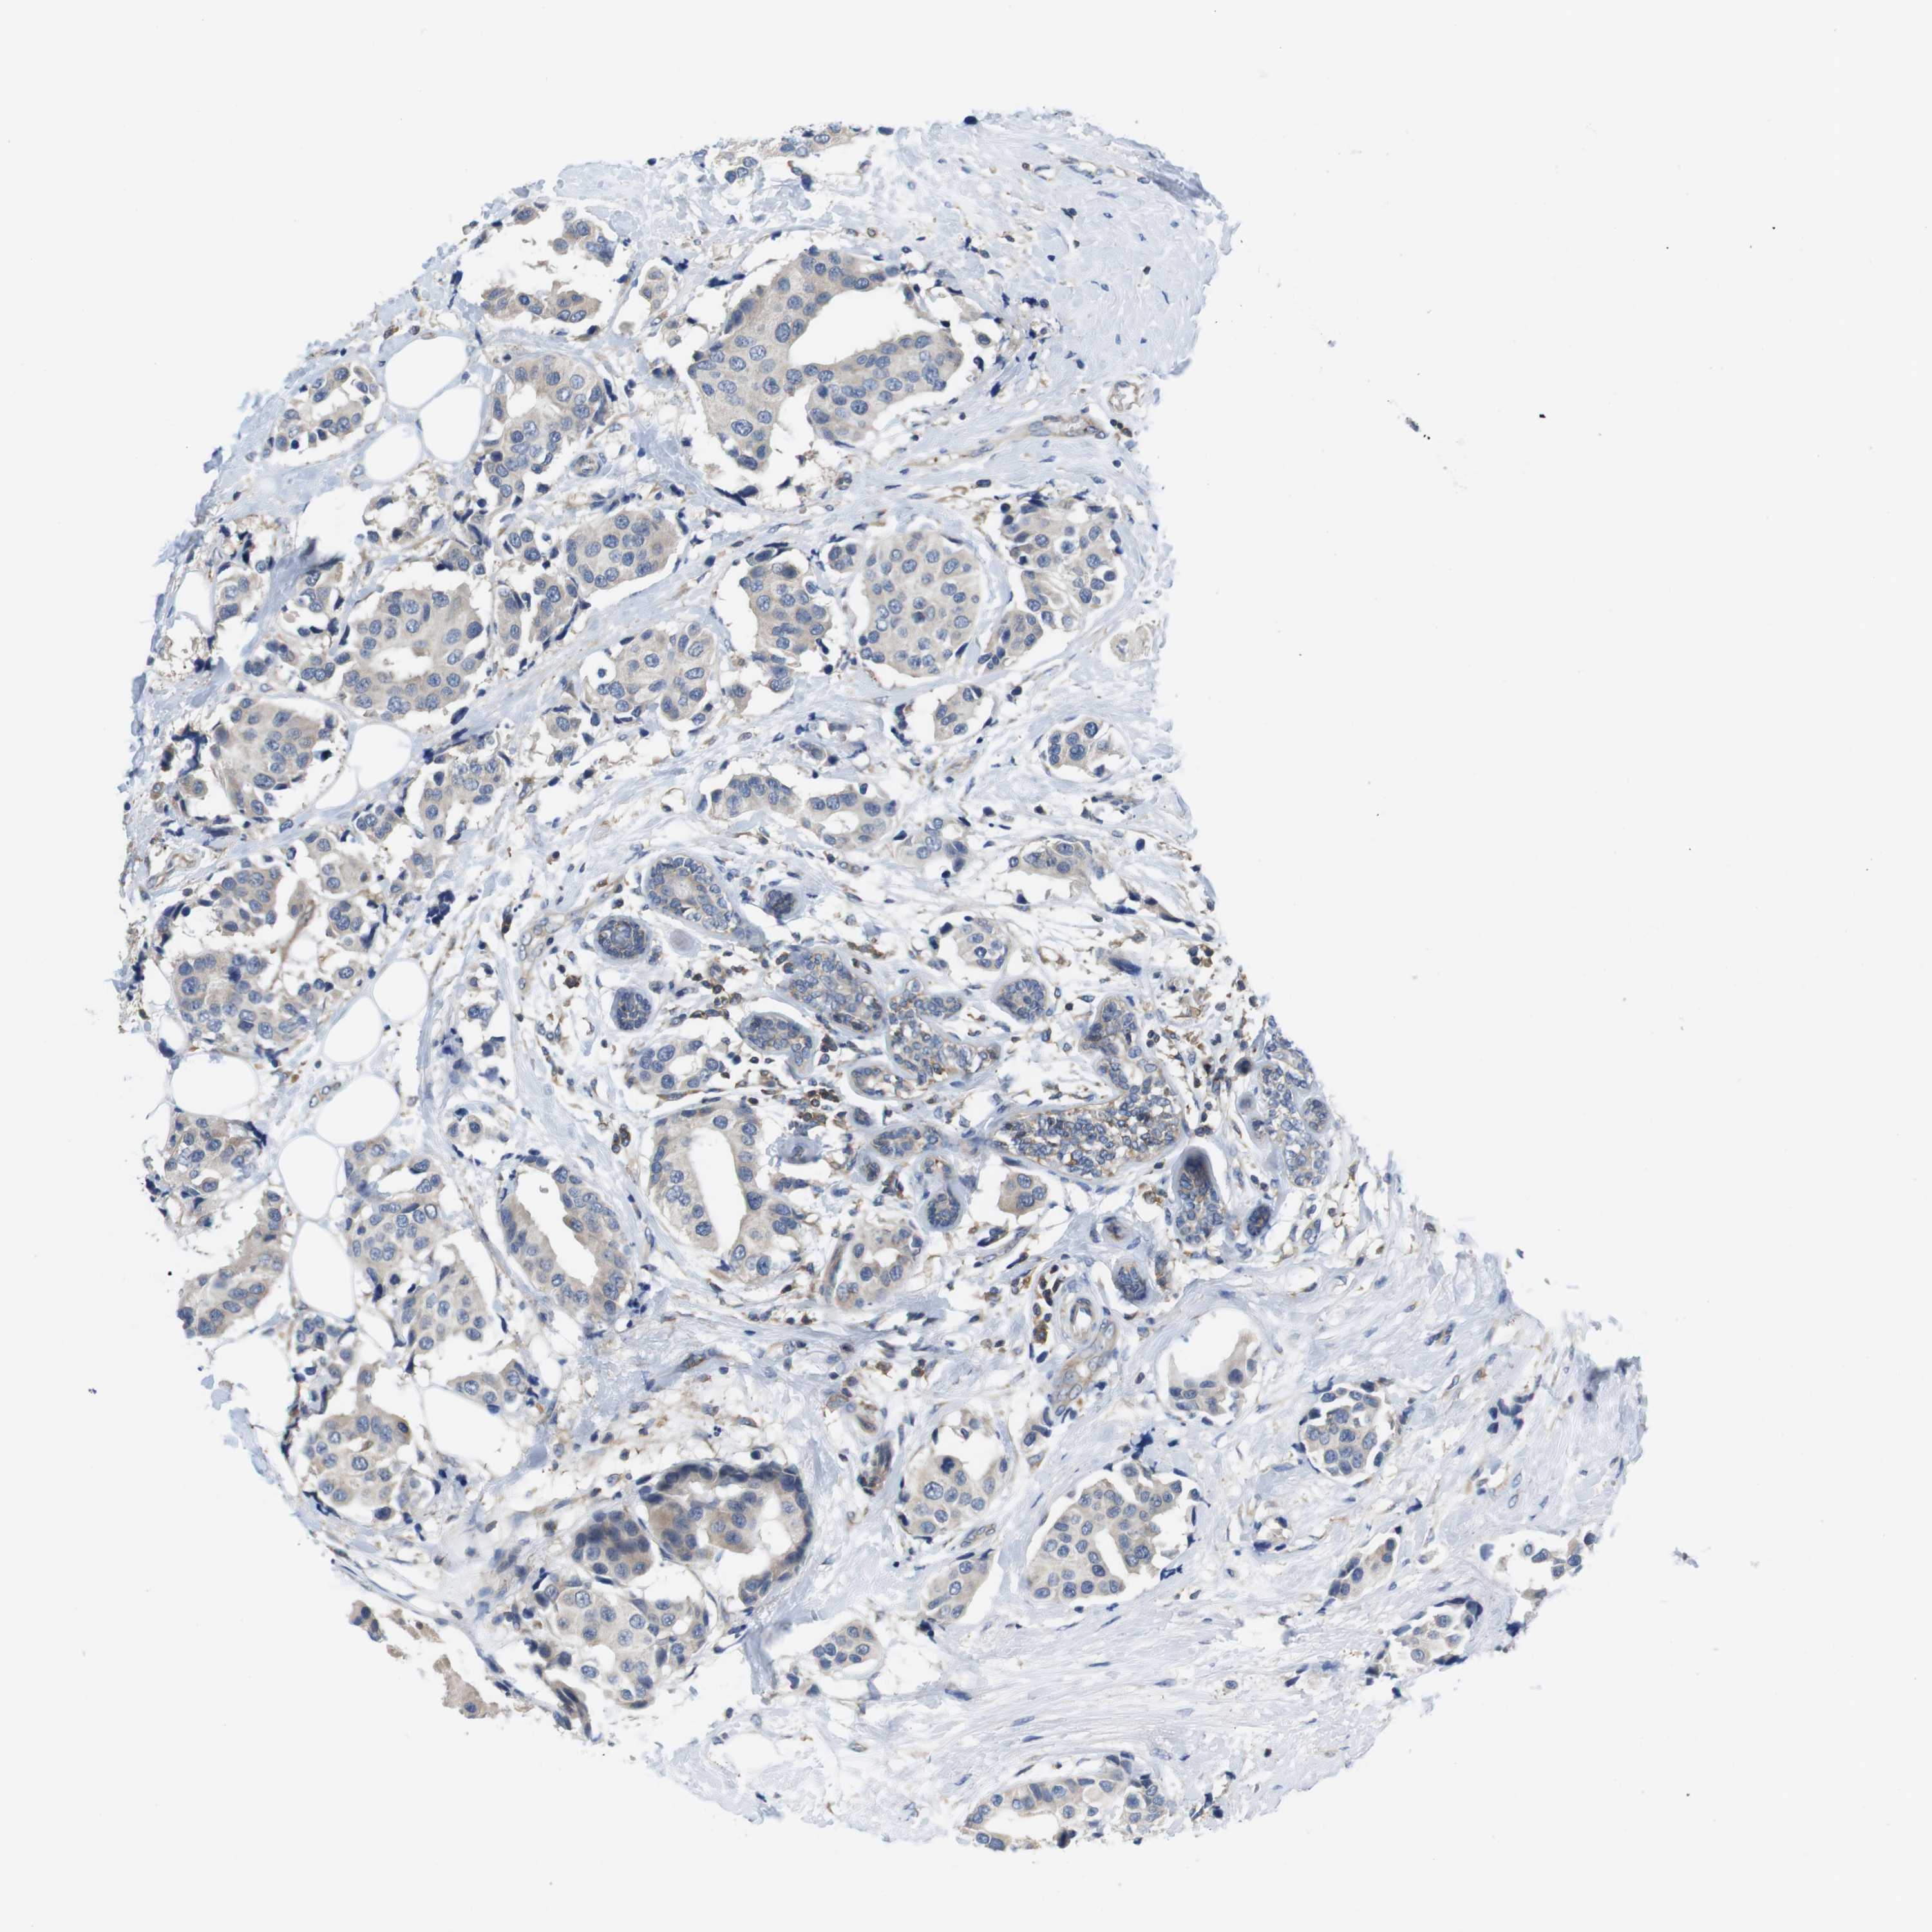

CANCER BREAST CANCER Show tissue menu

BRCA TCGA BRCA VALIDATION PROTEIN EXPRESSION